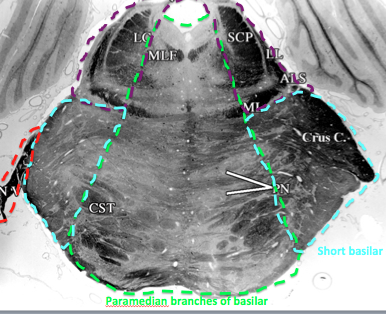

what supplies rostral medial medulla? until when?

paramedian branches of basilar. once you get to the mouse ears

What supplies olivary complex in the caudal to middle medulla?

vertebral

when does the anterior spinal replaced? what replaces it to feed middle rostral medulla?

when CN 8 comes in

replaced by paramedian branches of basilar

when does AICA first appear?

in rostral medulla when CN 8 comes in

in the medulla it just supples dorsal cochlear nucleus and the CN 8